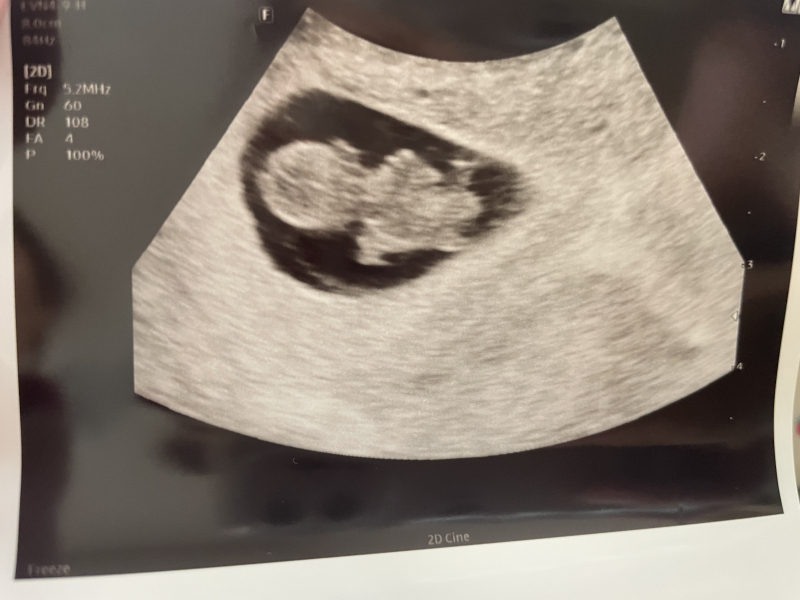

「排卵日が遅れたのか、小さい」と言われ、赤ちゃんの大きさで週数を決めようと思っていると言われています。いまだに週数はわかりません。11/11に受診をした際、心拍の確認を2週間後だとまだわからないかもれない、3週間後(12月2日)に来るでもいいと言われその日にすることにしました。ですが鮮血やレバーのような塊が出るので11/21に急遽受診しました。前回の先生とは違う人で、中で出血が起こりそうな何かがあるわけではなさそうと言われその時にモニターでぴこぴこと点滅している映像をみせてもらい、心拍も確認できるよと言われました。でもまぁひとまず今日は出血の内容の受診なので改めて予定通りの2日にきてくださいといわれました。その日から出血は続いていて、今日受診すると、大きくなってる写真をもらいました。正直毎日の出血に絶望していたのでこんなにしっかりカタチに育ってると思わなくて感動しました。可愛いです。しかし「排卵日が遅れたのかな、赤ちゃんの大きさで週数を決めようと思ってるんだけど、心拍が前回確認してるとあるんだけどー…なのでまた1週間後にきてください。」と言われました。理解が追いつかず、先生が言った言葉をオウム返ししてしまいましたが、「うん、なので今はなんとも言えません。」とも言われました。パニックで心拍が確認できないとは言われてないような、言われたのか、何も覚えてないです。もうだめということなのかとたびたび泣けてきて何も手につかないです。